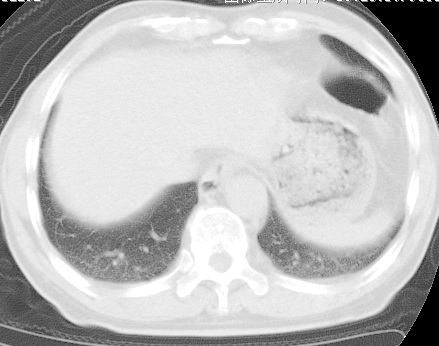

考虑右肺中叶不张,请大家发表意见

右肺中叶不张、肺门轮廓增大,占位不除外;建议增强,必要时支气管镜详查。

右肺中叶支气管闭塞,中叶肺不张,右侧肺门见肿块影。中心型肺癌的可能大。建议支气管镜检查。

右中叶体积明显缩小,且其支气管未显示,先考虑:中心型肺癌班右中叶肺不张。

建议:支气管镜检查。

考虑右肺中叶中央型肺癌并右肺中叶肺不张;建议:行纤支镜检查。

右肺门旁类圆形肿块影,右肺中叶不张,建议纤支镜检查。

1右肺门旁类圆形肿块影,右肺中叶不张,建议纤支镜检查

2右侧胸膜增厚,右侧叶间胸膜区钙化

3右肺下叶小囊状透亮影考虑肺气肿